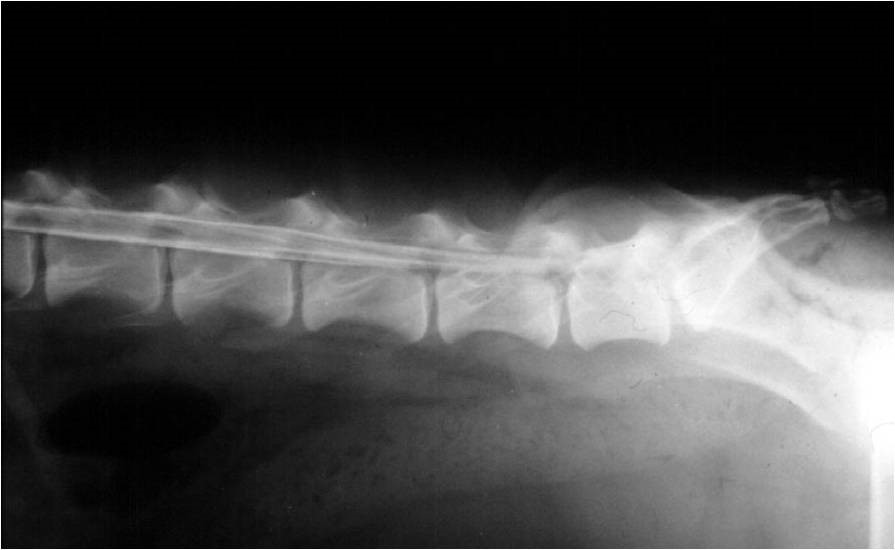

Lumbalis szakasz negatív myelogram